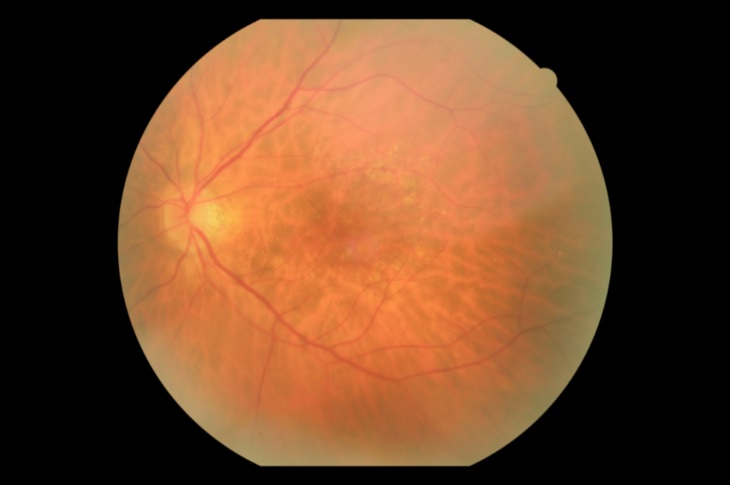

Друзи в макулата. Нативна снимка преди 2RT:

Намаляване на друзите след 2RT: